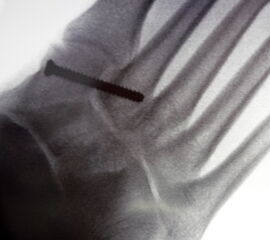

Patienten mit einer isolierten Verletzungen des Lisfranc Ligaments Grad II und III (n. Nunley) profitieren von einer operativen Therapie (Abb. 13).

Zum Lesen der Bildbeschreibung und zur Vollansicht bitte das Bild anklicken.

Bei frischen Verletzungen gelingt meist die geschlossene Reposition durch eine Repositionszange unter Bildverstärkerkontrolle. Anschließend wird über eine kleine mediale Inzision ein Kirschnerdraht vom Os cuneiforme mediale in die Metatarsale II-Basis gebohrt und das Lisfranc-Ligament durch eine Stellschraube in anatomischer Stellung ruhiggestellt. Durch weitere Schrauben lässt sich bei Bedarf das Tarsometatarsale I-Gelenk und der Raum zwischen Os cuneiforme I und II stabilisieren. Nach Lagekontrolle unter dem Bildverstärker wird eine durchbohrte Schraube mit durchgehendem Gewinde eingebracht (Abb. 14). Von der Verwendung von Zugschrauben wird abgeraten, da diese eine unnötige und unphysiologische Kompression der Gelenkflächen erzeugen.